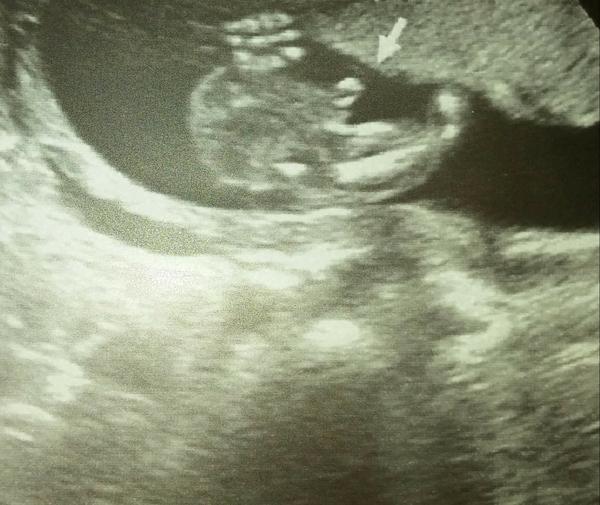

Ahoj maminky a budoucí maminky 😉 Prosím, poradila byste mi některá, co vidíte na fotce z ultrazvuku ve 20. týdnu za pohlaví? Určitě jste foteček viděly už mraky, proto vás žádám o radu...Nechci nikoho ovlivnit, proto svůj tip řeknu později 🙂 Děkuju moc!!!

Dole je zadek asi a nohy ma smerem doprava, ma je za hlavou..

@vanocni_stromecek Rekl, ze vidi holcicku, ale ze si neni jistej pak se po chvilce k.tomu vratil a rekl, zase holcicku..a dneska jsem projizdela utz video a prave co jsem zakrouzkovala, mi prislo jak pindik :D, ale zase kdyz to tes vidim, tak mi to prijde moc velky..a pod tim by to mohla bejt pipi, takovy to kavovy zrnko jak popisuji.. sama nevim a jsem zvedava :D